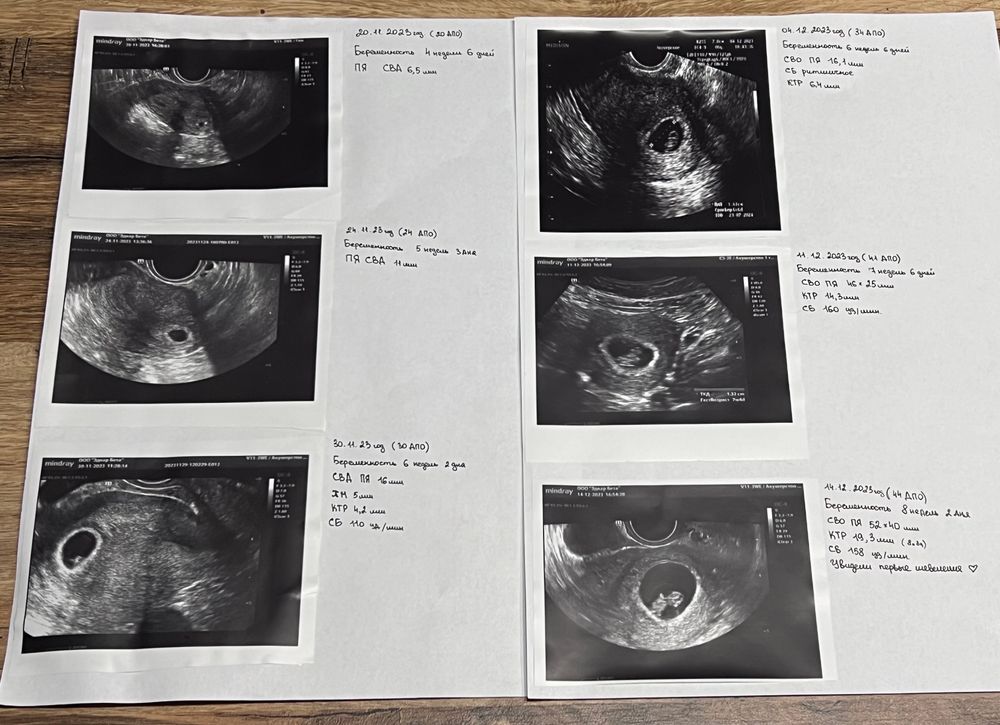

Девчат, может кому будет полезно🙌🏽💓 Когда сб нашли и Эмбриончик🥹

Всем привет🥰 Вчера были на узи) нашли наконец сб, 110 ударов в минуту 😍 Эмбриончиу визуализируется😋 Я так рада!! Срок 6 и 2